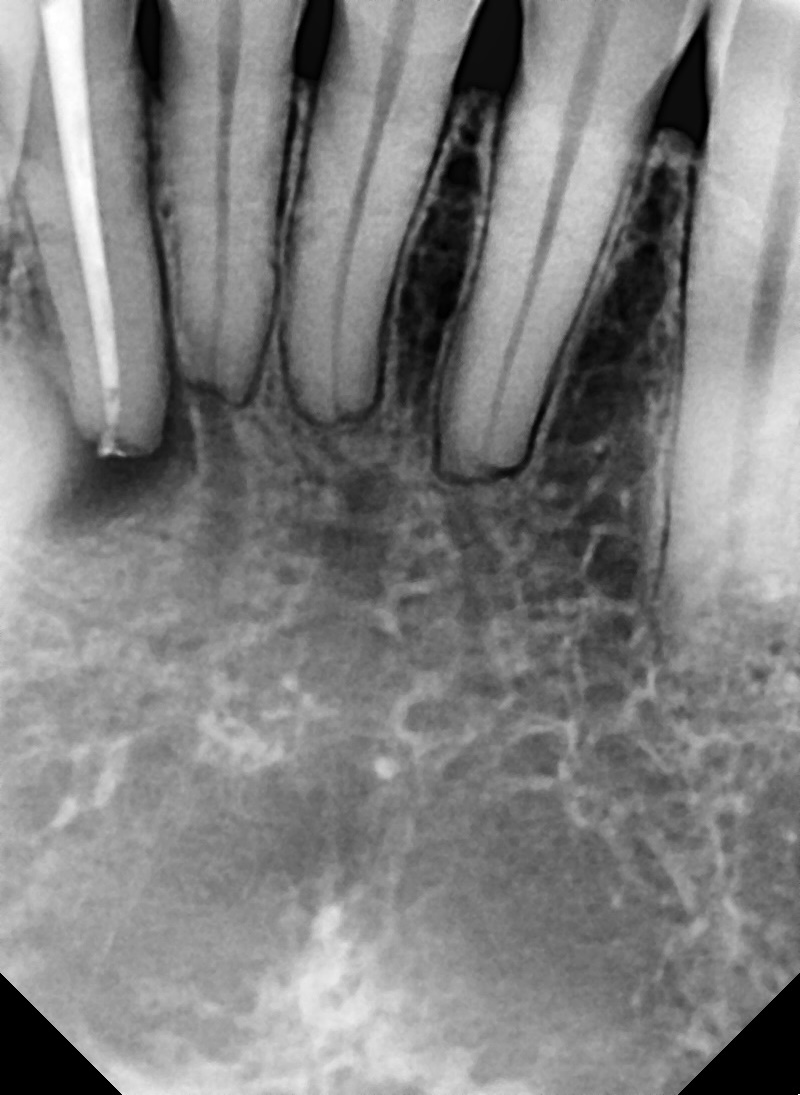

수술 전

수술 후

치근단 절제술 사례

전후사진